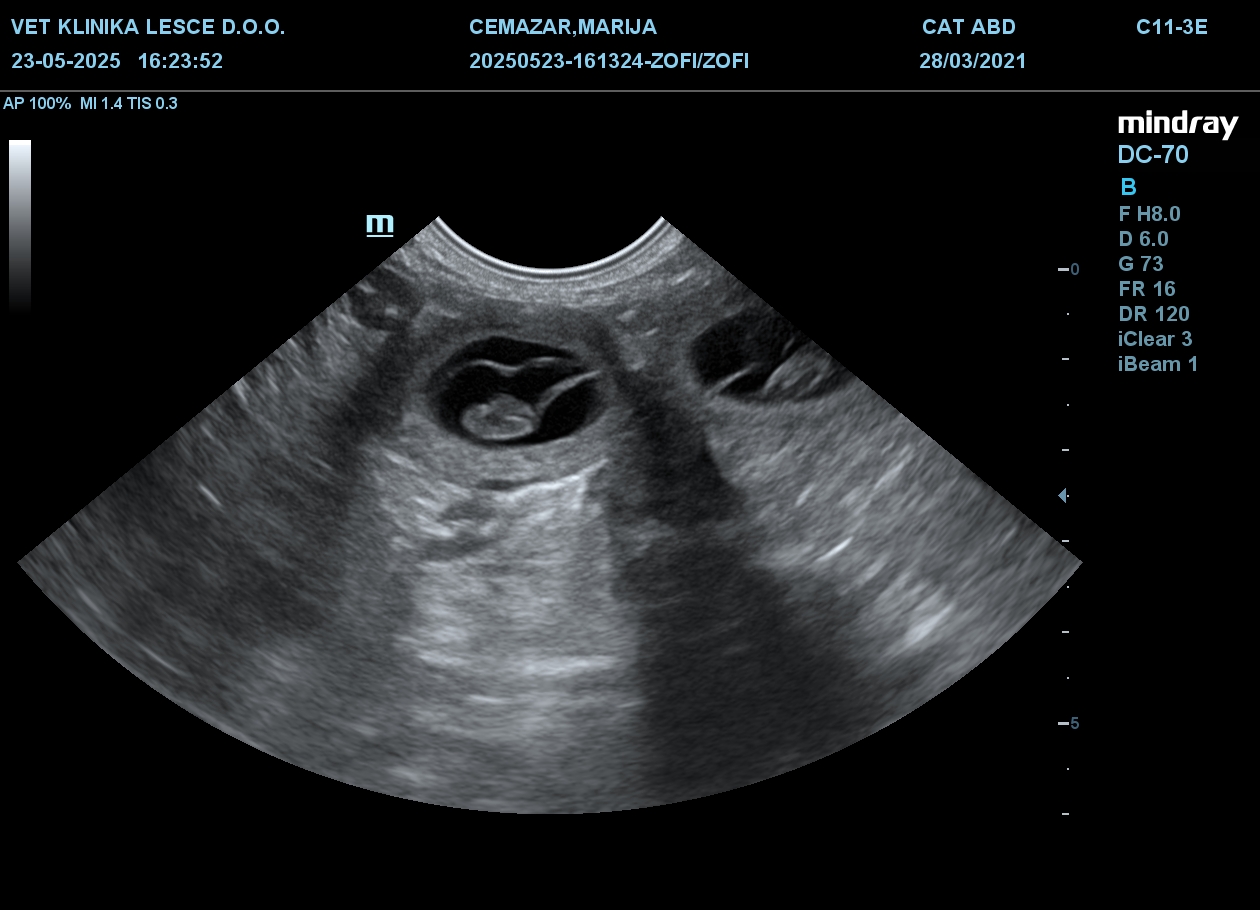

Z veseljem najavljamo, da naša draga Zala Zophie pričakuje mladičke! Predviden datum kotitve je 29. 6. 2025 in že nestrpno čakamo, da na svet pozdravimo dragocene kepice veselja in ljubezni.

Dam/Mati: Zala Zophie Grand Calvera

Klicno ime: Zophie

Datum rojstva: 28. 3. 2021

Zophie brejost preživlja zdrava in vesela, mi pa vsi skrbimo, da bo mladičke pričakala v varnem in udobnem okolju. Pričakujemo, da se bo v mladičih odražal čudovit temperament in ljubeča osebnost tako Zophie kot Watzmanna, ki oba prihajata iz odličnih psarn in linij, ki v Sloveniji še niso prisotne.